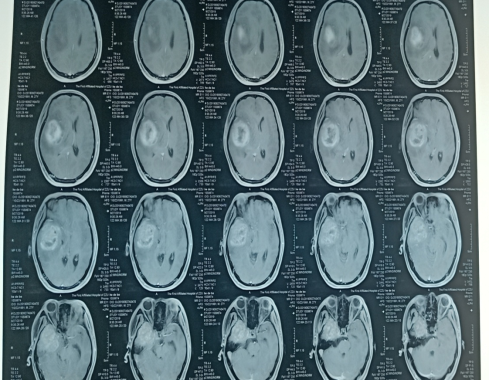

2020.07.30三门峡市中心医院:右侧颞叶胶质瘤术后改变,右侧颞叶异常强化影,与0512日片对比强化灶较前明显,大小无明显变化。

2020.09.01右侧颞部胶质瘤术后改变,颞叶病灶强化程度较前减弱。左侧颞部结节状强化影,大致同前。

2020.12.08三门峡市中心医院:右侧颞叶胶质瘤术后改变,病变范围较前增大,新见脑桥、右侧额叶强化,考虑肿瘤复发可能。

2021.01.08三门峡市中心医院:右侧颞叶胶质瘤术后改变,右额叶病灶较前增多,原脑干、右侧额叶病灶较前体积增大,考虑肿瘤进展。